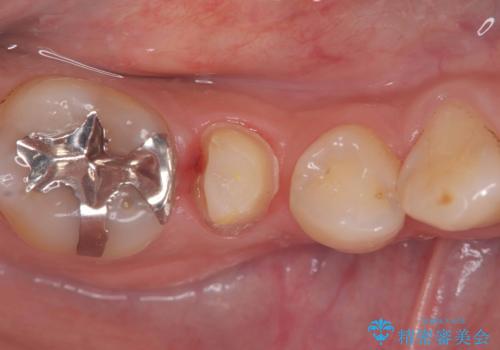

- 虫歯が大きく歯が欠けている状態でした。 そこに食べ物も詰まっている状態でした。

虫歯を除去後、精密根管治療を行い、オールセラミッククラウンで治療を行いました。

虫歯が大きく神経まで到達していました。将来根尖性歯周炎にならないよう徹底的に神経をとり洗浄したうえで被せ物をしています。